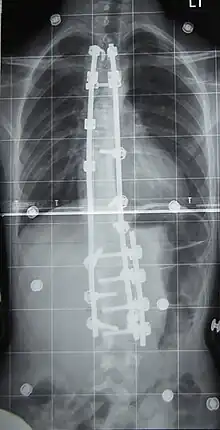

L'indication concerne environ 10 % des scolioses idiopathiques du sujet jeune[2] et concerne les scolioses importantes, avec un angle de Cobb dépassant les 50°. La technique consiste en la mise en place de deux longues tiges métalliques vissées dans les vertèbres, permettant le redressement de la colonne vertébrale, notamment avec la technique et le matériel de 3e génération proposés par Cotrel et Dubousset[45]. Les complications sont essentiellement locales mais il peut exister des étirements ou compressions de racines nerveuses dans moins d'un pour cent des interventions[46].